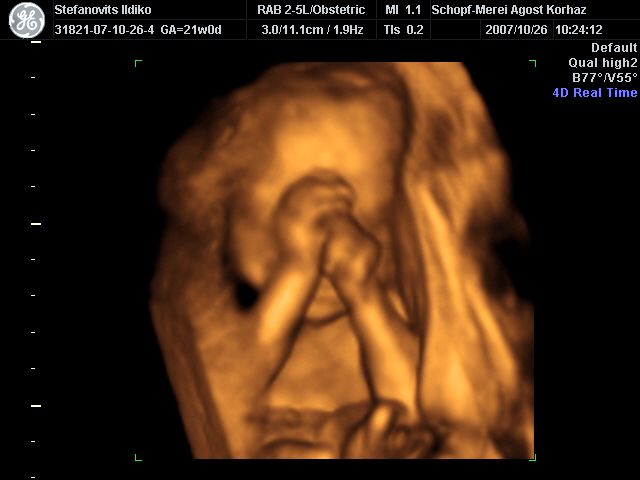

4D Ultrahang - 21+1 (07/10/26, Bp.)

4D - 4